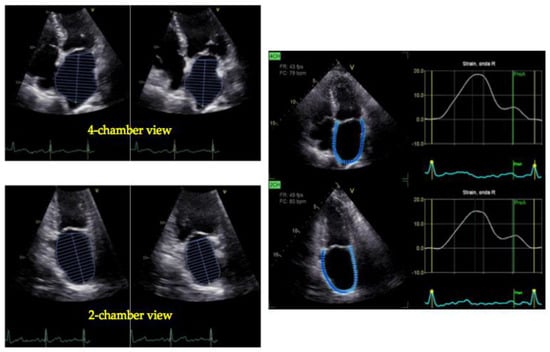

3. Left Atrial Ejection Fraction (LAEF)